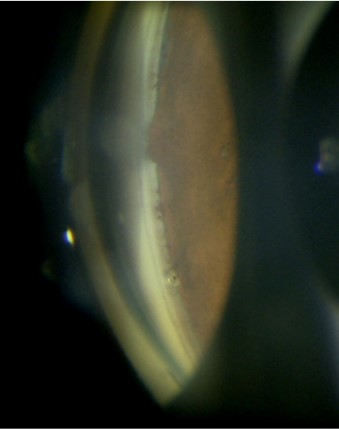

水晶体再建術併用眼内ドレーン挿入術で両眼にiStent inject Wを挿入。右上方はPASができたため1個閉じてしまった。しかし半年経った現在も緑内障点眼薬なしで眼圧17mmHgで安定している。